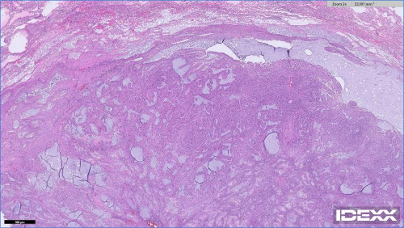

03 강아지 폐종양 조직검사 결과

수술 후 조직검사 결과 종양은 완전히 절제되었으며 전이 소견 없음으로 판정되었습니다.

울산 강아지 폐종양 수술 후 조직검사 / 출처: 에스동물메디컬센터

✔️ 종양 종류: 폐암(Pulmonary carcinoma)

✔️ 분화도: 중등도 분화 (Moderately differentiated)

✔️ 등급: Grade 2 (총점 10점)

✔️유사분열 수: 4/2.37mm² (낮은 편)

✔️ 혈관 침습: 없음

✔️ 절제연: 깨끗하게 제거(가장 가까운 절제연 3mm)

폐암 중증도 분화란?

​암세포가 정상 세포와 얼마나 유사한지 판단함에 있어 일부는 정상 폐세포와 유사하지만 일부는 암세로포 인해 비정상적인 구조도 함께 보이는 형태 * 환자는 에스동물메디컬센터에서 수술 후 본래 병원(1차 병원)에서 폐 종양 관리를 이어갔습니다 *